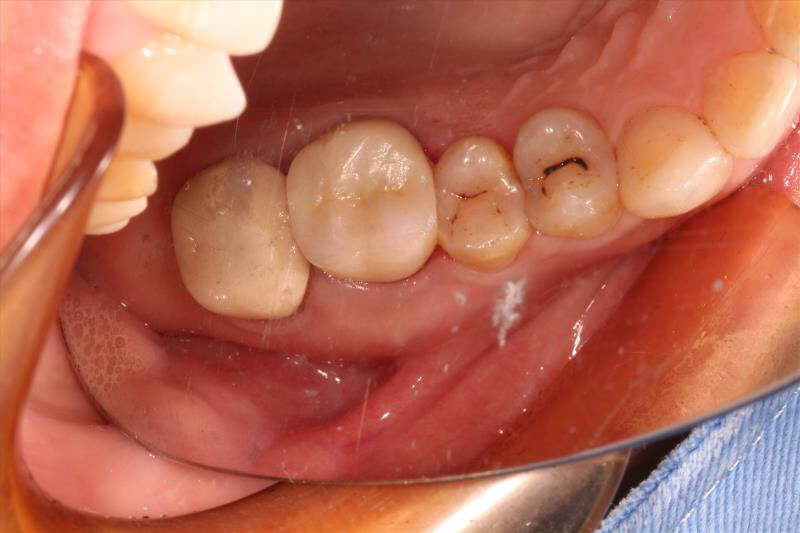

患者中年女性,右上6外院根管治疗多年,近期牙龈红肿,咀嚼疼痛,X线检查见根尖区大面积低密度影响,怀疑有遗漏的根管没有清理,用铒激光无损拆掉牙冠后进行根管再治疗,找到了遗漏的MB2,妥善的根管治疗完成后,重新戴上之前拆掉的牙冠,即解决了疼痛又为患者节省了一笔费用。